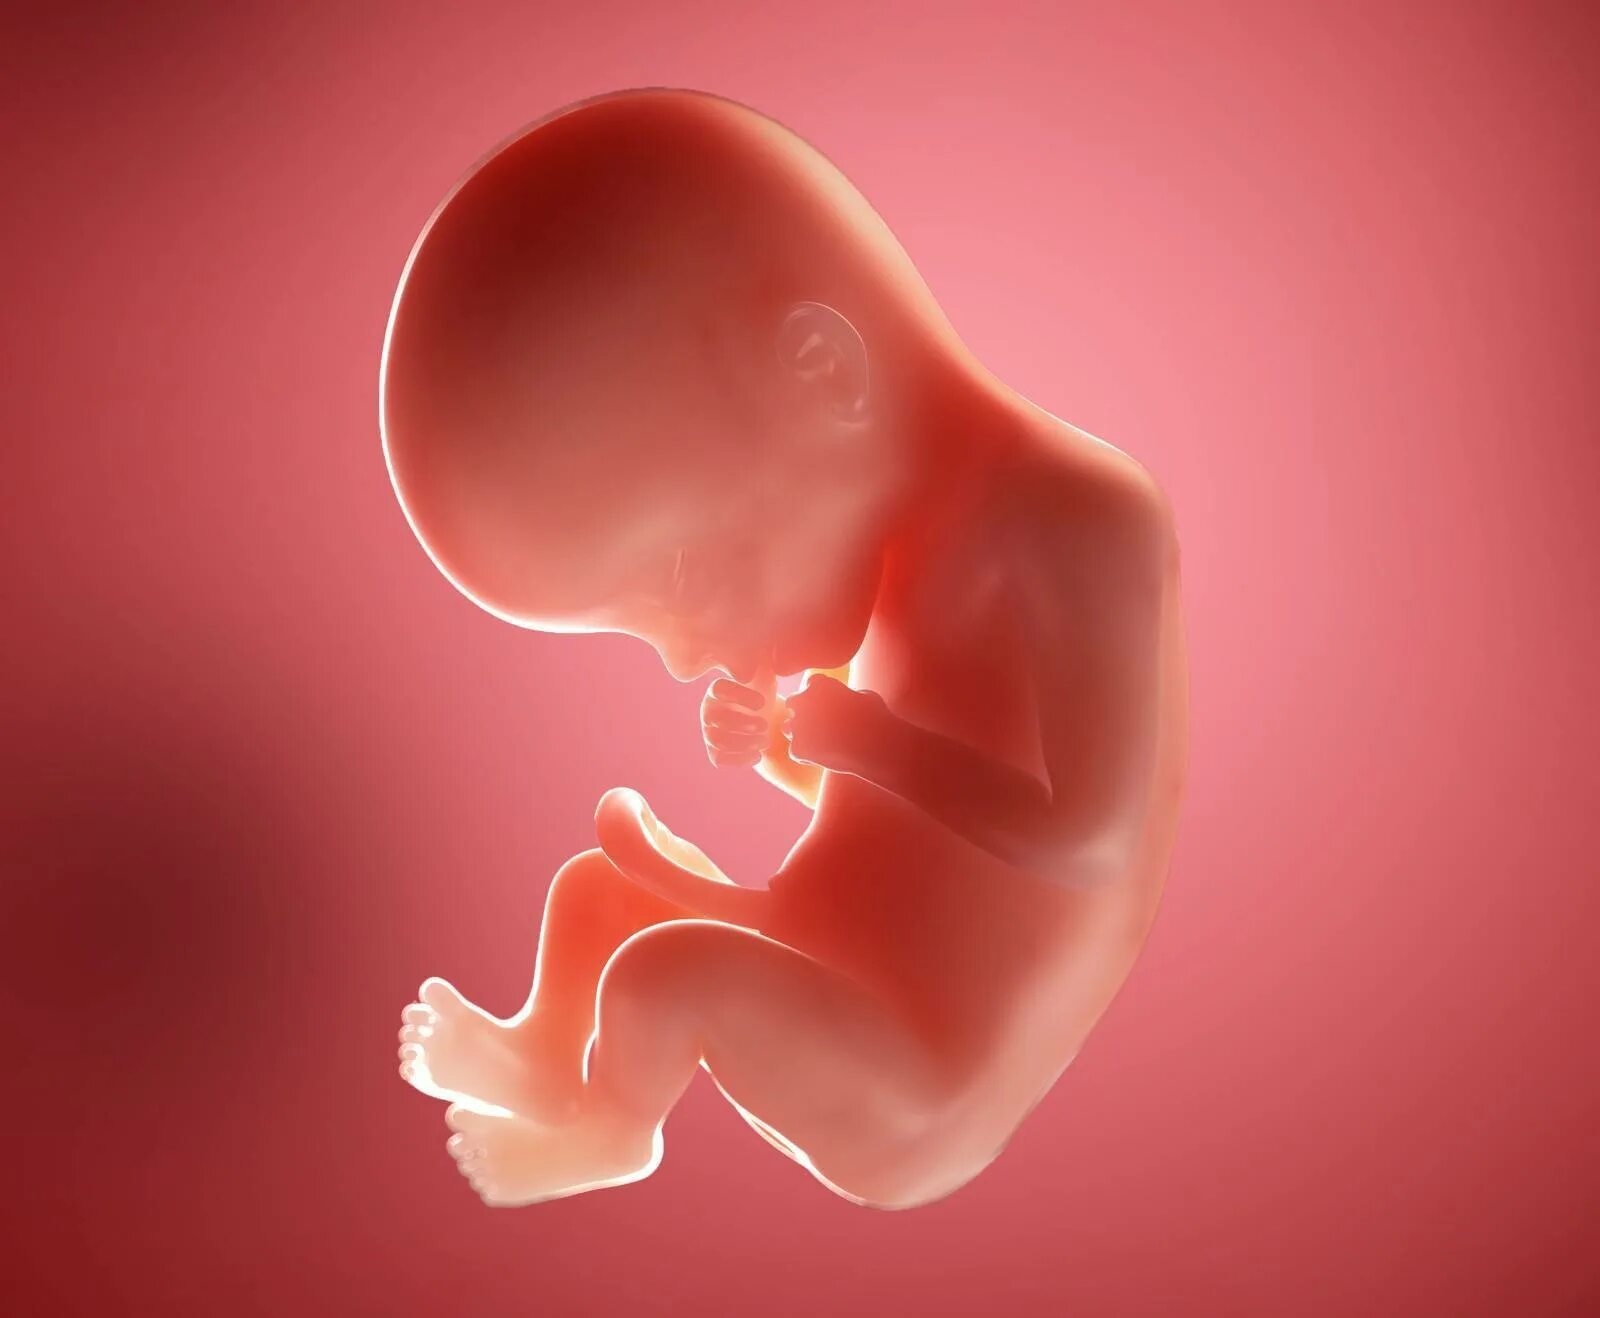

Ребенок в животе 22 недели